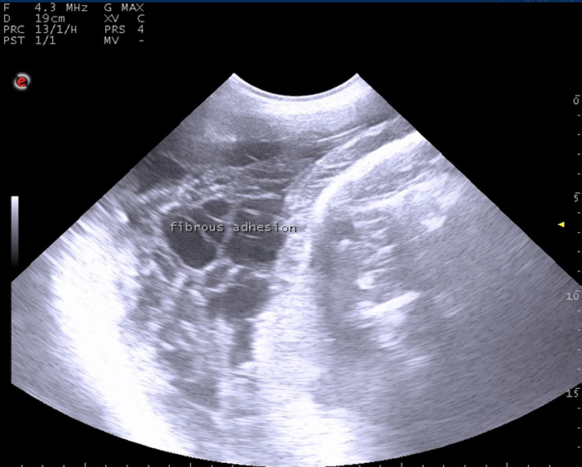

Out of the 75 uterine torsion affected cases, fifty buffaloes (66.67%) responded successfully to the rolling procedure, and followed by complete cervical dilatation and vaginal fetal delivery (Table 1), while 17 buffaloes (22.67%) responded successfully to the rolling procedure and followed by incomplete cervical dilatation. And only eight buffaloes (10.67%) failed to respond to the rolling procedure due to the presence of uterine adhesion with adjacent organs, so these animals were culled due to extensive parametritis and peritonitis after ultrasonographic examination (Fig. 1).

Fig. 1. Ultrasonographic examination with trans-abdominal probe at frequency 3.5–5 MHZ showing long standing uterine torsion case with severe degree at full term suffered from failure of detorsion due to presence of uterine adhesion with fibrin threads.

Our study reported that the degree and duration of uterine torsion from its occurrence till its presentation can influence the prognosis of uterine torsion affected animals. This result is consistent with the early findings which showed that the prognosis of uterine torsion cases is highly influenced by the degree and duration of uterine torsion and the presence of signs of approaching of parturition (Prabhakar et al., 1995; Schonfelder et al., 2005). We also reported that cases suffered from severe degree and prolonged duration of uterine torsion developed extensive uterine adhesion with adjacent abdominal organs with massive parametritis and peritonitis and did not respond to the detorsion procedure. Thus, these cases were culled because caesarean section was not useful in these cases. Because incision of the uterus during cesarean operation in prolonged cases of uterine torsion leads to drain of uterine content into abdominal cavity resulting into severe peritonitis and eventually death of dam (Purohit et al., 2013).